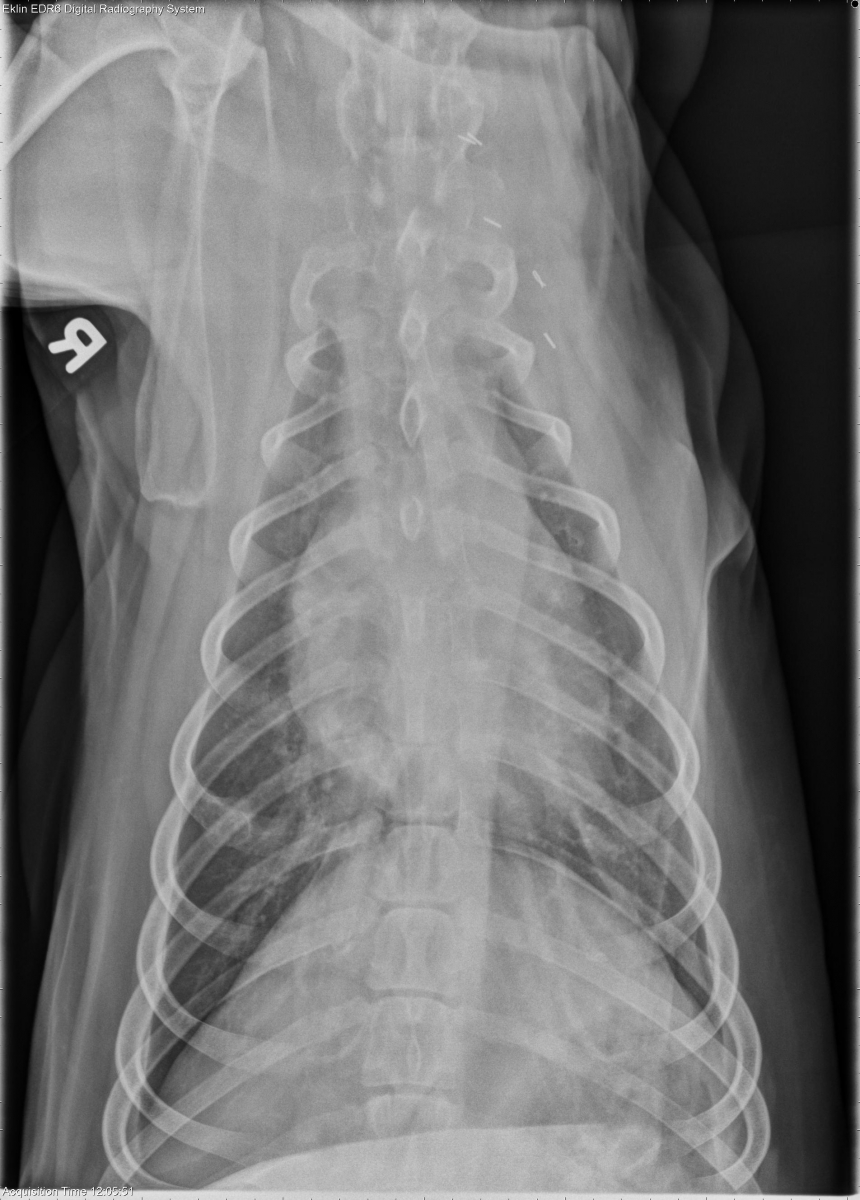

Today’s case is a 6 year old male Spaniel with previous amputation performed for left thoracic limb osteosarcoma. What are your findings?

The left thoracic limb is absent, and there are metallic staples in the soft tissues consistent with previous amputation. The cardiovascular structures are normal in size and shape. No abnormalities are seen in the pulmonary parenchyma, pleural space, or mediastinum. The first sternebra is radiolucent and irregular in appearance with subtle periosteal reaction. On the dorsoventral projection, there is expansion and lysis of the right 6th rib. These findings are confirmed on collimated projections. There is osteophyte production surrounding the right shoulder joint.

Osteosarcoma metastasis to the right 6th rib and first sternebra.